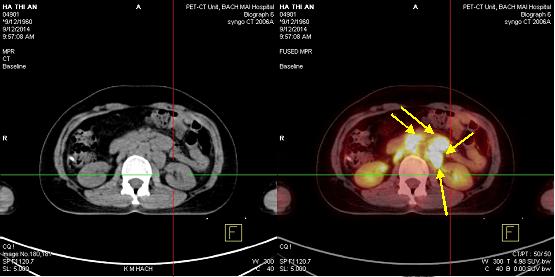

Bệnh nhân được chụp PET/CT nhằm mục đích đánh giá giai đoạn bệnh cho thấy: Hình ảnh tăng hấp thu dược chất phóng xạ tại hạch thượng đòn trái, thành dạ dày, cổ xương đùi phải, và hạch ổ bụng.

Hình 3: Hình ảnh dày thành dạ dày, tăng hấp thu 18F-FDG, max SUV: 3,74 (mũi tên đỏ).

Hình 4: Hình ảnh nhiều tổn thương di căn hạch ổ bụng tăng hấp thu 18F-FDG, kích thước từ 2,1- 8,8cm, max SUV: 8,52 (mũi tên vàng)